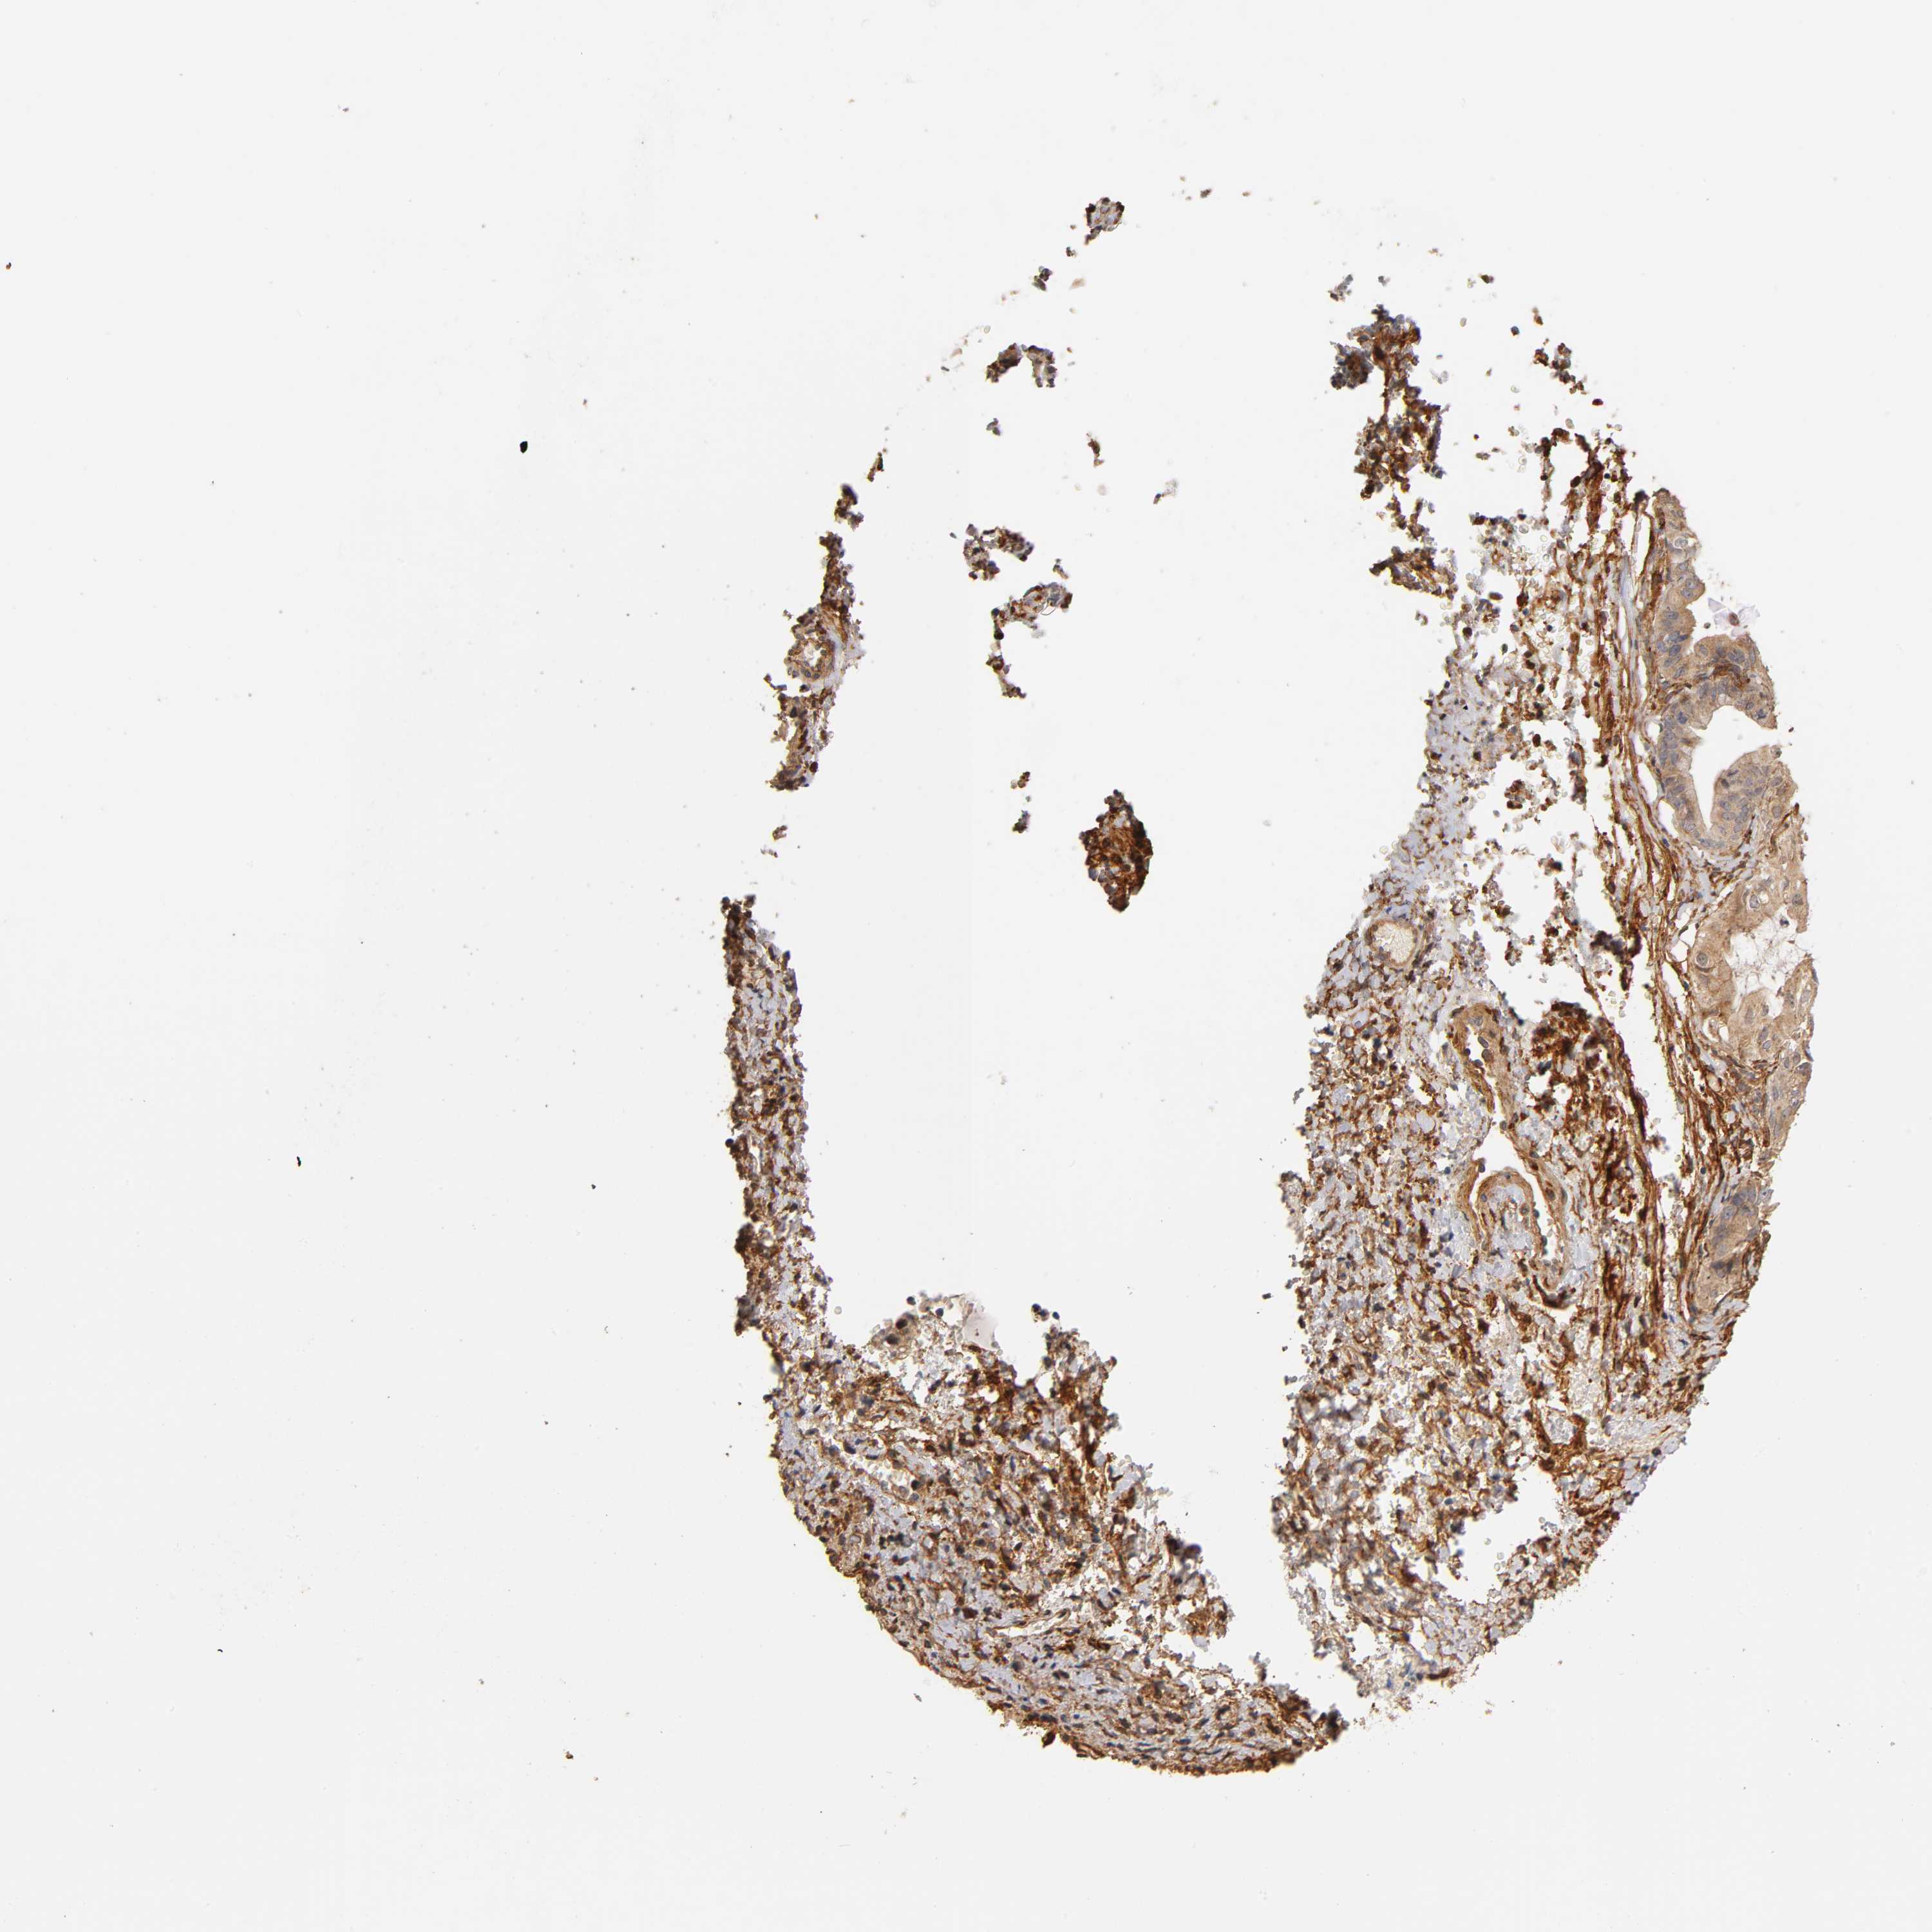

OVARIAN CANCER - Protein expressioni

A mouse-over function shows sample information and annotation data. Click on an image to view it in a full screen mode. Samples can be filtered based on level of antibody staining by selecting one or several of the following categories: high, medium, low and not detected. The assay and annotation is described here.

Note that samples used for immunohistochemistry by the Human Protein Atlas do not correspond to samples in the TCGA dataset.

Antibody stainingi

Antibody staining in the annotated cell types in the current human tissue is reported as not detected, low, medium, or high, based on conventional immunohistochemistry profiling in selected tissues. This score is based on the combination of the staining intensity and fraction of stained cells.

Each image is clickable and will lead to virtual microscopy that enables deeper exploration of all samples and also displays staining intensity scores, fraction scores and subcellular localization as well as patient and tissue information for each sample.

Antibody HPA004056

Staining

High

Medium

Low

Not detected

Cystadenocarcinoma, serous, NOS